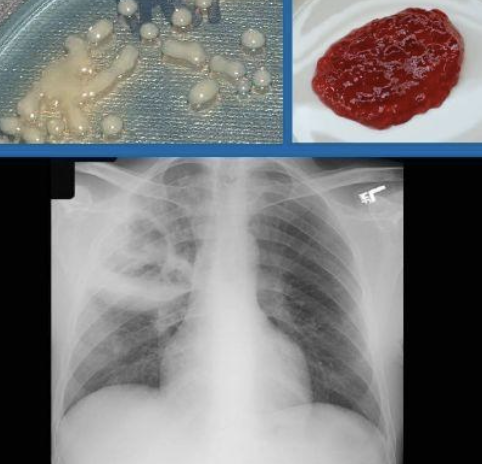

Tuberculosis

Ziehl–Neelsen (ZN) stain → used to identify acid-fast organisms such as members of the genus Mycobacterium. Definitive diagnosis is with sputum culture not microscopy